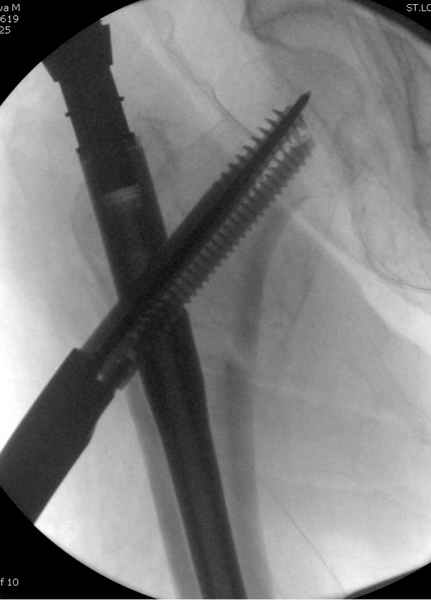

В общем, сделали. См. приложение.

Длина и из-за этого ось получились не совсем такие, как хотелось бы, все-таки срок после той операции уже 6 недель. Может быть, стоило провести дистракцию аппаратом неделю-другую. Заранее спасибо за комментарии и критику.

Александр, поздравляю от души, отличная работа, вообще-то и у меня тоже были опасения по поводу латеральной стенки. Идеальное показаниt к применению импланта закрытым методом при таких переломах, когда болт замыкается в штифте, конструкции придается угловая жесткость, примерно как в Blade Plate.

Здесь сканнированные снимки импланта и операционные снимки больной.

На этом снимке процесс компрессии нижним болтом.

Итог